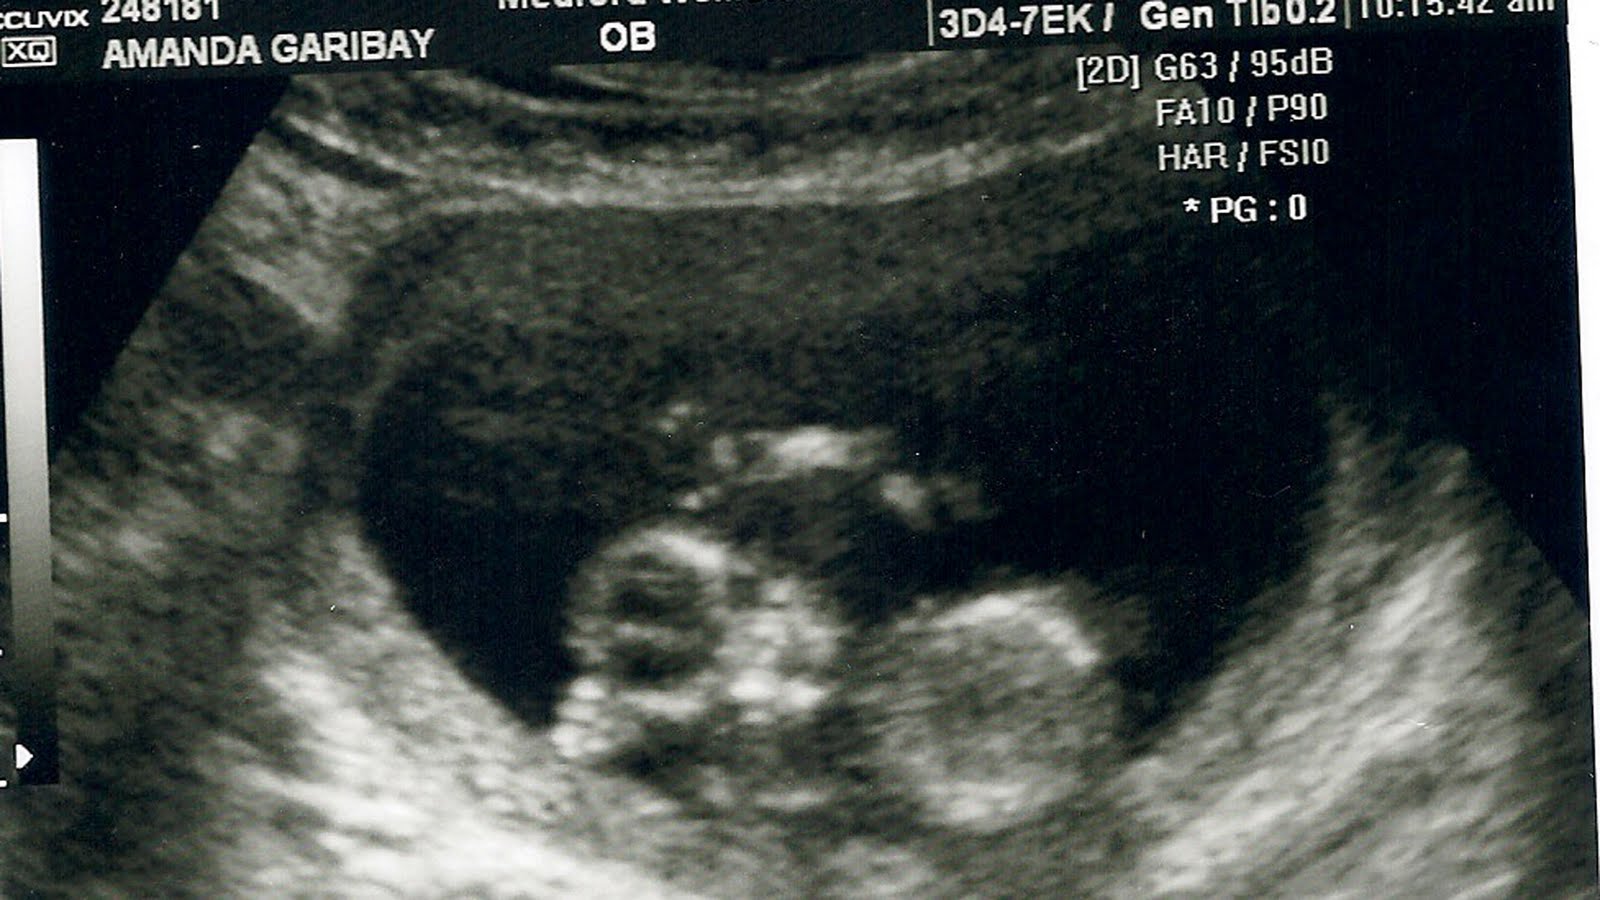

12 Weeks, 4 Days and counting!

This pregnancy is going really well. We’re already in the 2nd trimester and my throwing up is finally coming to a halt (thanks so much to the drugs my OB prescribed me). Between the throwing up and my complete loss of an appetite to any food that isn’t a fruit or a vegetable has put my weight gain to a whopping -10 lbs. YUP ~ I’ve lost 10 pounds this pregnancy… and I’m not complaining!

We’ve been fortunate to see the baby a few times already throughout this pregnancy, and the latest was yesterday. And I fell head over heels IN LOVE! The baby was moving all around and had its hands above its head ~ complete cuteness! I even have a picture here for you to see.

Ella is completely convinced that it’s a boy, I’m convinced it’s a girl, and Jayden’s praying it’s a boy. Gino doesn’t care… he just wants his cuddle bear here.

So, here’s the u/s pic from yesterday. If you look you can see the head, the body the baby’s arms over its head and you can even see its little fingers. Pure love coming from this mama’s heart!